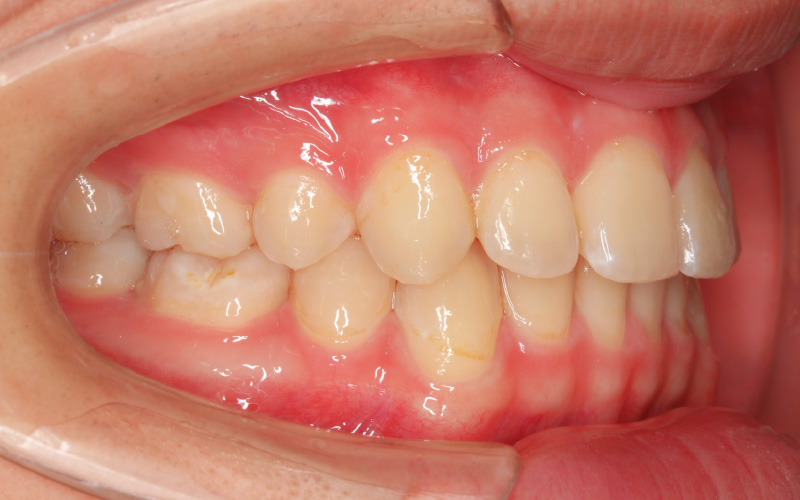

矯正治療後

[16歳4か月]

上下顎前歯の前突があり、口元が出ていましたので小臼歯の抜歯を行いました。抜歯で得たスペースと、下顎の反時計回転の成長メカニクスを用いて、歯並びと顔立ちを整えていきました。

その結果、オトガイは前方に出て、口唇は後方に引っ込み、鼻尖・オトガイ・口唇の位置に良いハーモニーが生まれました。顔もソフィストケートされ、顔立ち・歯並びともにバッチリです。